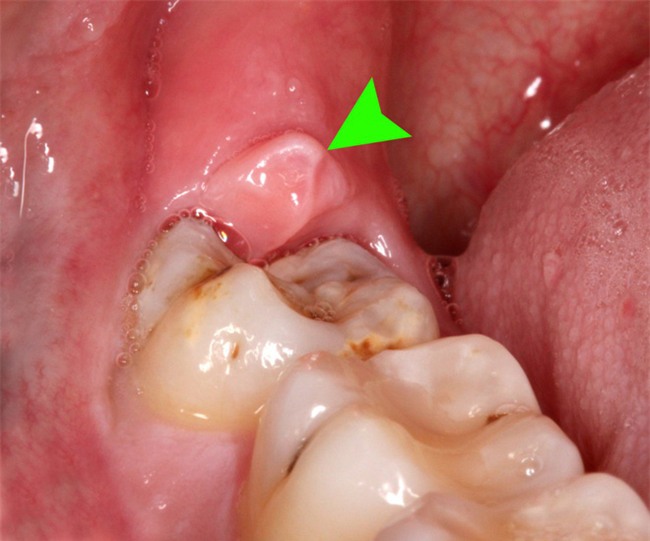

Răng khôn có thể gây ra biến chứng rất nguy hiểm

1. Viêm lợi trùm, viêm mô tế bào: Các răng mọc lệch gây nhồi nhét thức ăn, vùng này lại rất khó vệ sinh làm sạch nên lâu ngày gây nên hiện tượng viêm nhiễm, sưng đỏ, đau quanh thân răng, viêm lợi trùm, sau đó tạo túi mủ (áp xe), cứng hàm.